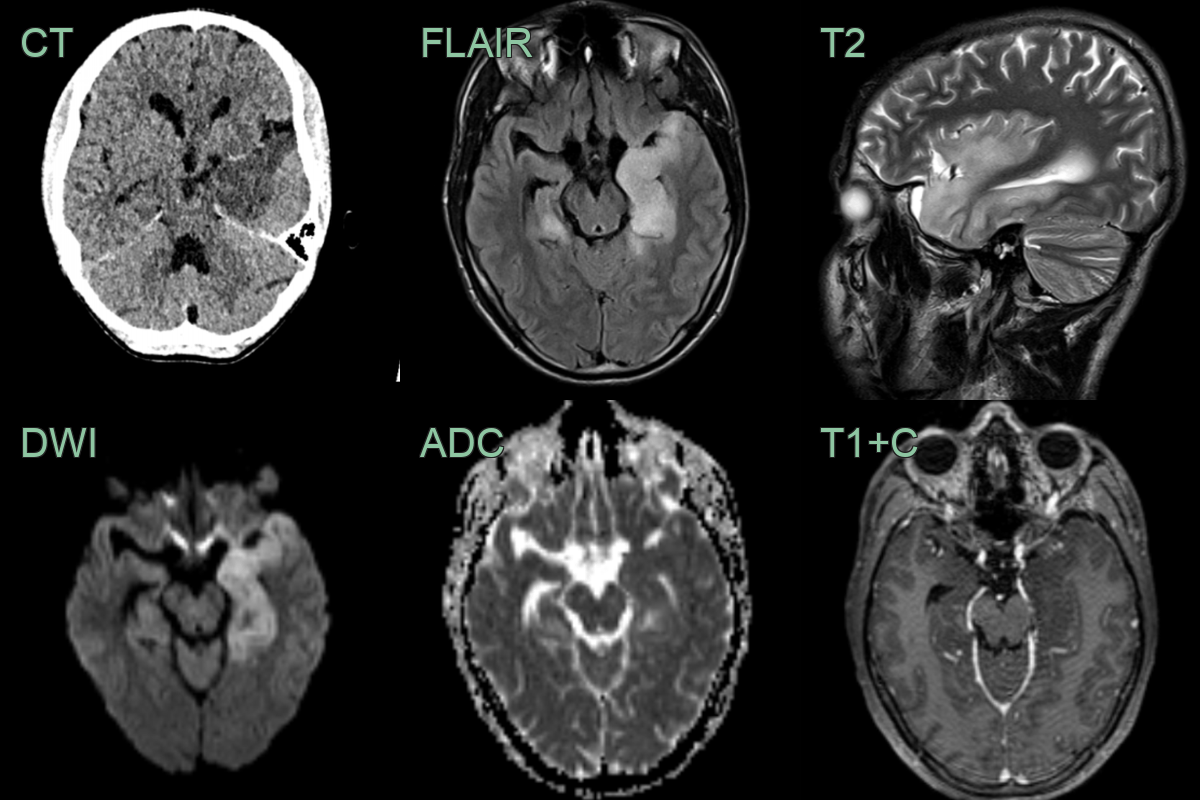

• 50-year-old patient presented with headache and confusion.

• CT showed swelling and low attenuation in the anterior and mesial left temporal lobe and in the right hippocampus.

• The parenchymal low attenuation gave the impression of a hyperdense vessel (Mach effect) but infarction was not likely as both MCA nad PCA territories were involved.

• There was high T2, FLAIR and DWI signal (without clear diffusion restriction) but no enhancement.